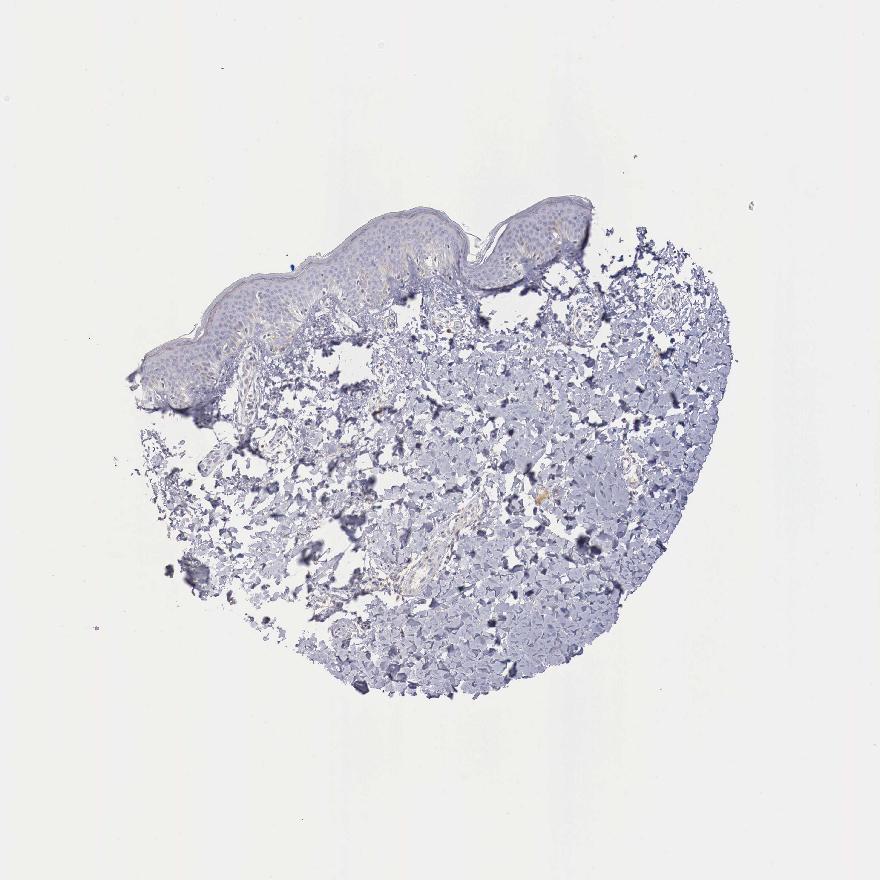

SKIN 1 - Antibody stainingi

Antibody staining in the annotated cell types in the current human tissue is reported as not detected, low, medium, or high, based on conventional immunohistochemistry profiling in selected tissues. This score is based on the combination of the staining intensity and fraction of stained cells.

Each image is clickable and will lead to virtual microscopy that enables deeper exploration of all samples and also displays staining intensity scores, fraction scores and subcellular localization as well as patient and tissue information for each sample.

Antibody HPA000339Antibody CAB025269

Langerhans Not detectedNot detected

Fibroblasts Not detectedNot detected

Keratinocytes Not detectedNot detected

Melanocytes Not detectedNot detected

SKIN 2 - Antibody stainingi

Antibody HPA000339Antibody CAB025136Antibody CAB025269

Epidermal cells Not detectedNot detectedNot detected